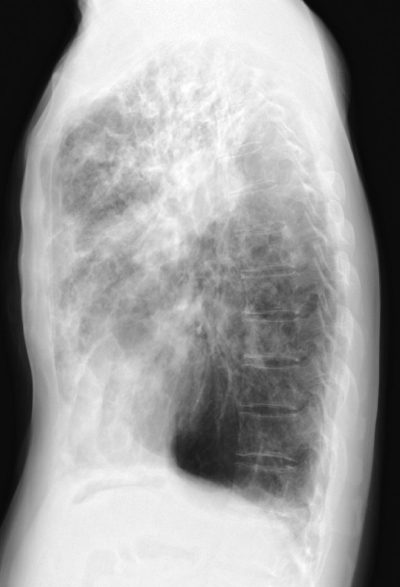

45 歳の男性。喀痰を主訴に来院した。1年前から茶褐色の細長い粘稠な痰をしばしば喀出するようになった。小児期から喘息で治療中である。胸部エックス線写真の正面像と側面像及び肺野条件の胸部 CTを別に示す。